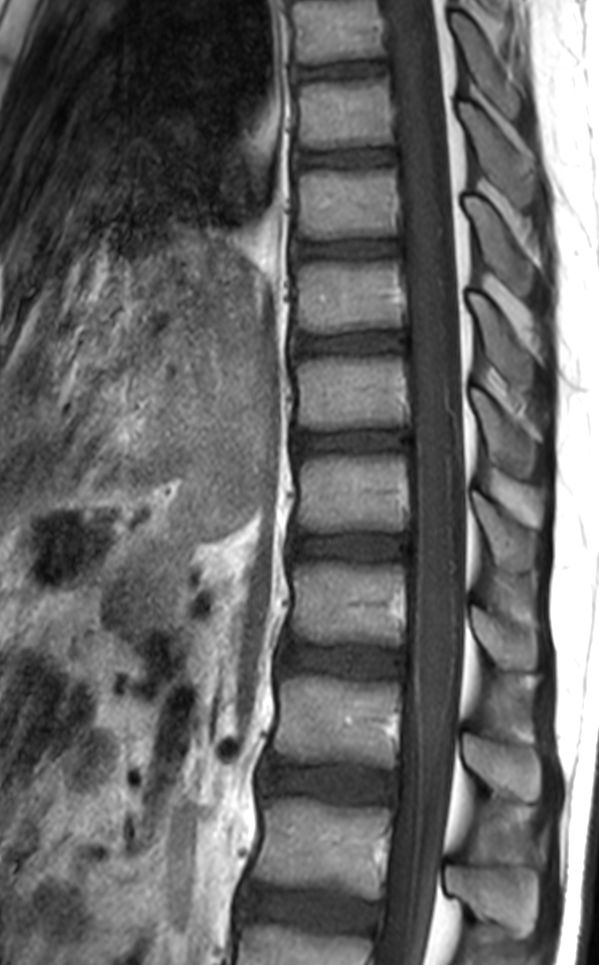

Sagittal T2w TSE (T-Spine)